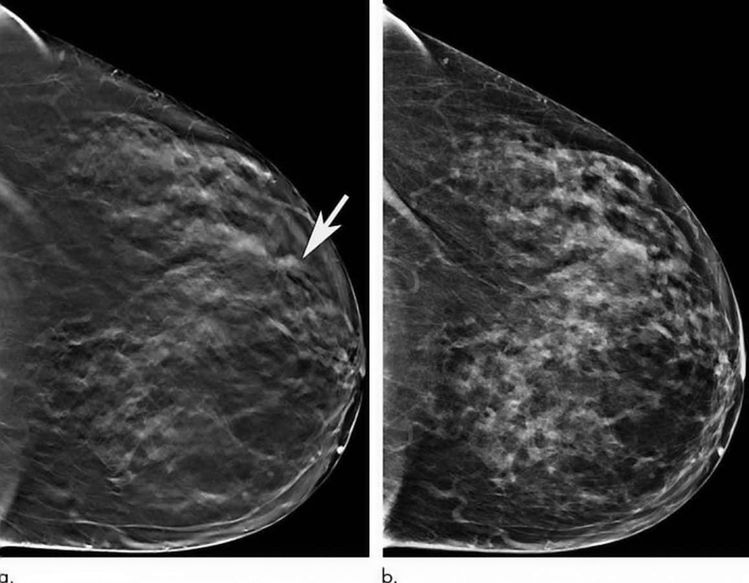

A high-tech system which produces 3D images of the breast helps doctors detect the early signs of cancer in older women, according to new research.

The technique called tomosynthesis (TOMO) also reduces the number of patients called back for a second scan because their first was unclear – which can be traumatising.

It takes lots of small images to create a 3D picture – enabling detection of more tumours earlier. For many women, this could be lifesaving.

Both approaches were highly effective but TOMO performed best – including producing fewer false-positive results where a tumour is incorrectly indicated.